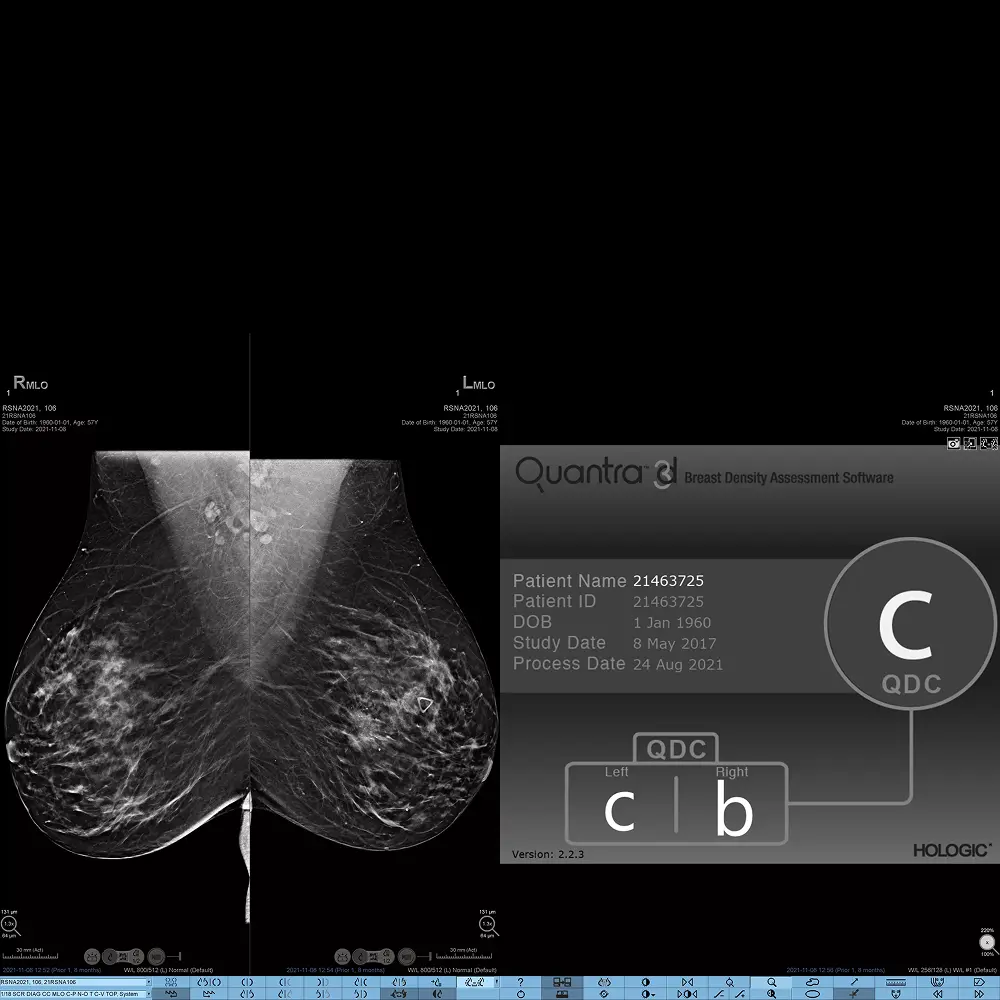

Quantra 2.2 è la soluzione di Intelligenza Artificiale avanzata di Hologic per la valutazione automatizzata e oggettiva della densità del tessuto mammario, un parametro sempre più riconosciuto come fattore di rischio per il cancro al seno. Questo software di ultima generazione offre una misurazione accurata, standardizzata e ripetibile, riducendo la soggettività tipica della valutazione visiva.

Rispetto alle versioni precedenti, Quantra 2.2 introduce algoritmi innovativi in grado di analizzare non solo la quantità di tessuto denso, ma anche struttura e forma della mammella. Il risultato è una valutazione più completa, che permette di adattare in modo più preciso il percorso diagnostico e clinico di ogni paziente.

- Classificazione secondo le categorie BI-RADS 5a edizione.